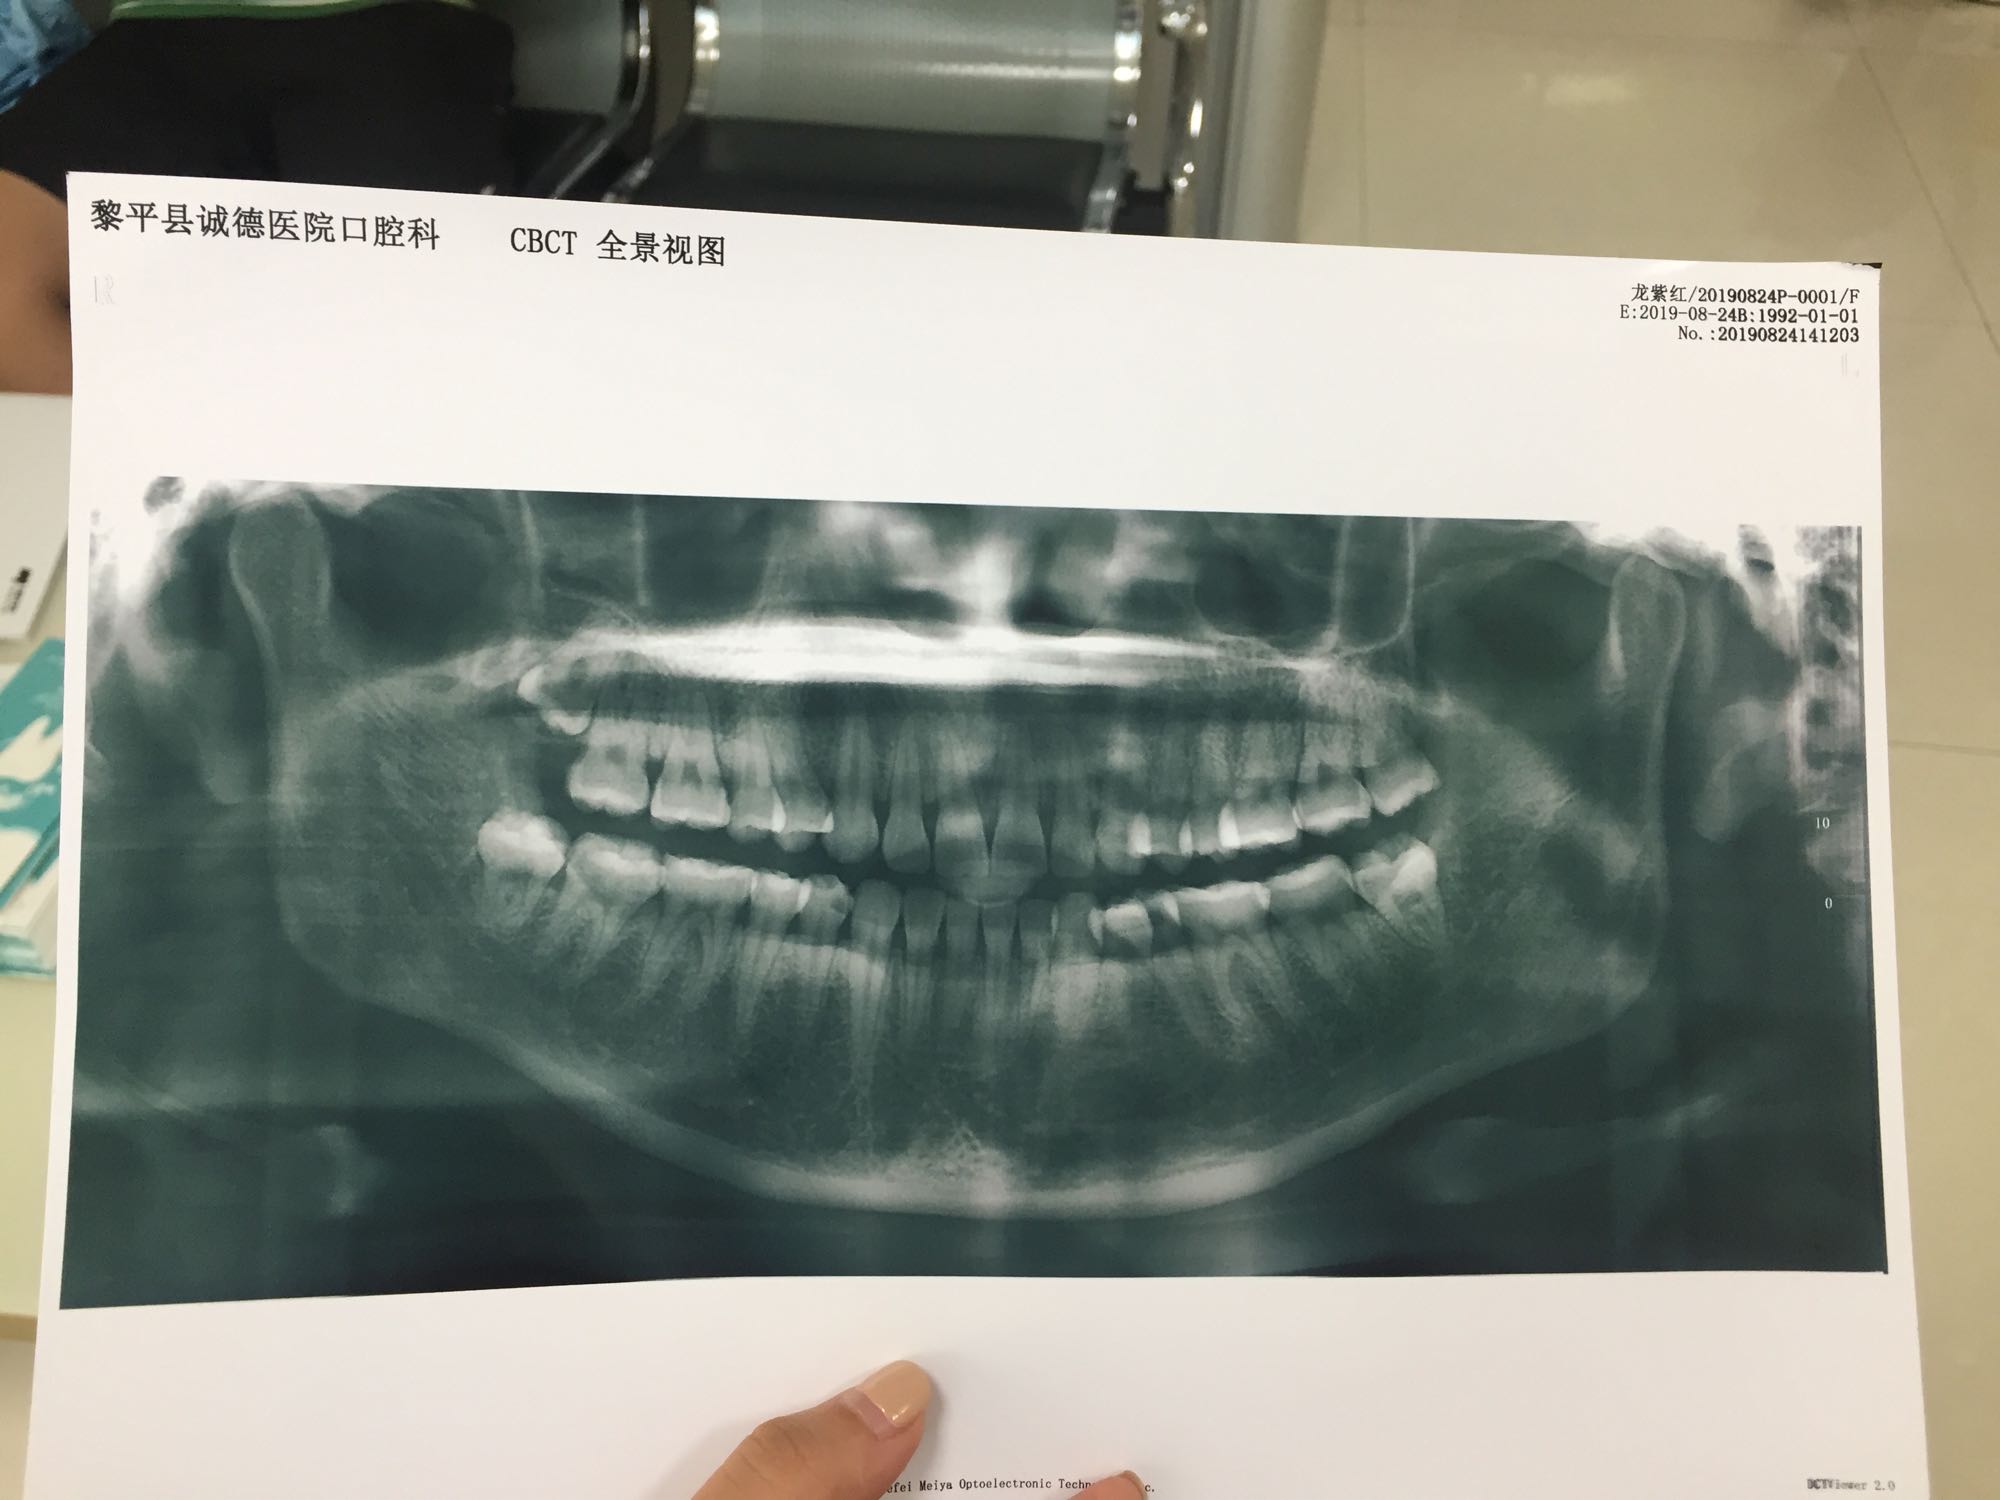

先去挂了个号,然后做了个血检。来到口腔科拍了牙片,看到我的牙齿长得还可以,没有像大多数拔智齿的长横。我的还是比较正的,难度不大,但是内心还是很恐惧的![[黑线]](/static/emoticons/u9ed1u7ebf.png)

先去挂了个号,然后做了个血检。来到口腔科拍了牙片,看到我的牙齿长得还可以,没有像大多数拔智齿的长横。我的还是比较正的,难度不大,但是内心还是很恐惧的